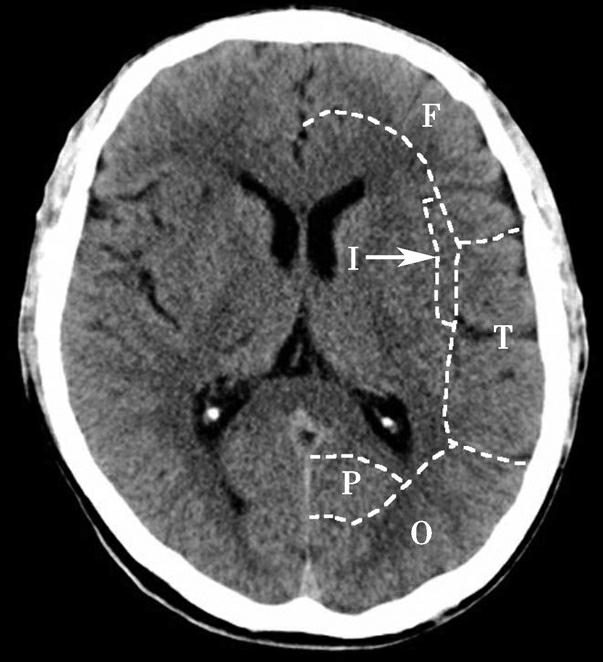

Alberta卒中项目早期CT评分(Alberta stroke program early CT score,ASPECTS)是一种评价急性缺血性卒中患者大脑中动脉供血区早期缺血性改变的简单、可靠、系统化的方法,是常用的脑卒中评定量表之一,可对缺血性病变快速进行半定量评价,有助于判定溶栓效果和远期预后。该评分主要基于CT平扫,具体分区如下(图1-2-76)所示,即选取大脑中动脉供血区2个层面。分区后共10个区域,每个区域记1分。评分时任何区域只要有低密度灶,则扣除该区域得分。正常脑ASPECTS评分为满分(10分),若MCA供血区广泛梗死累及全部区域时,则ASPECTS评分为0分。

图1-2-76 ASPECTS评分脑组织分区

A.在基底节层面(即丘脑和纹状体平面),分为各级分支M 1 、M 2 、M 3 、岛叶(缩写I)、豆状核(缩写L)、尾状核(缩写C)和内囊(缩写IC)后肢等7个区域;B.在基底节以上层面(基底节层面上2cm),包括M 4 、M 5 和M 6 。